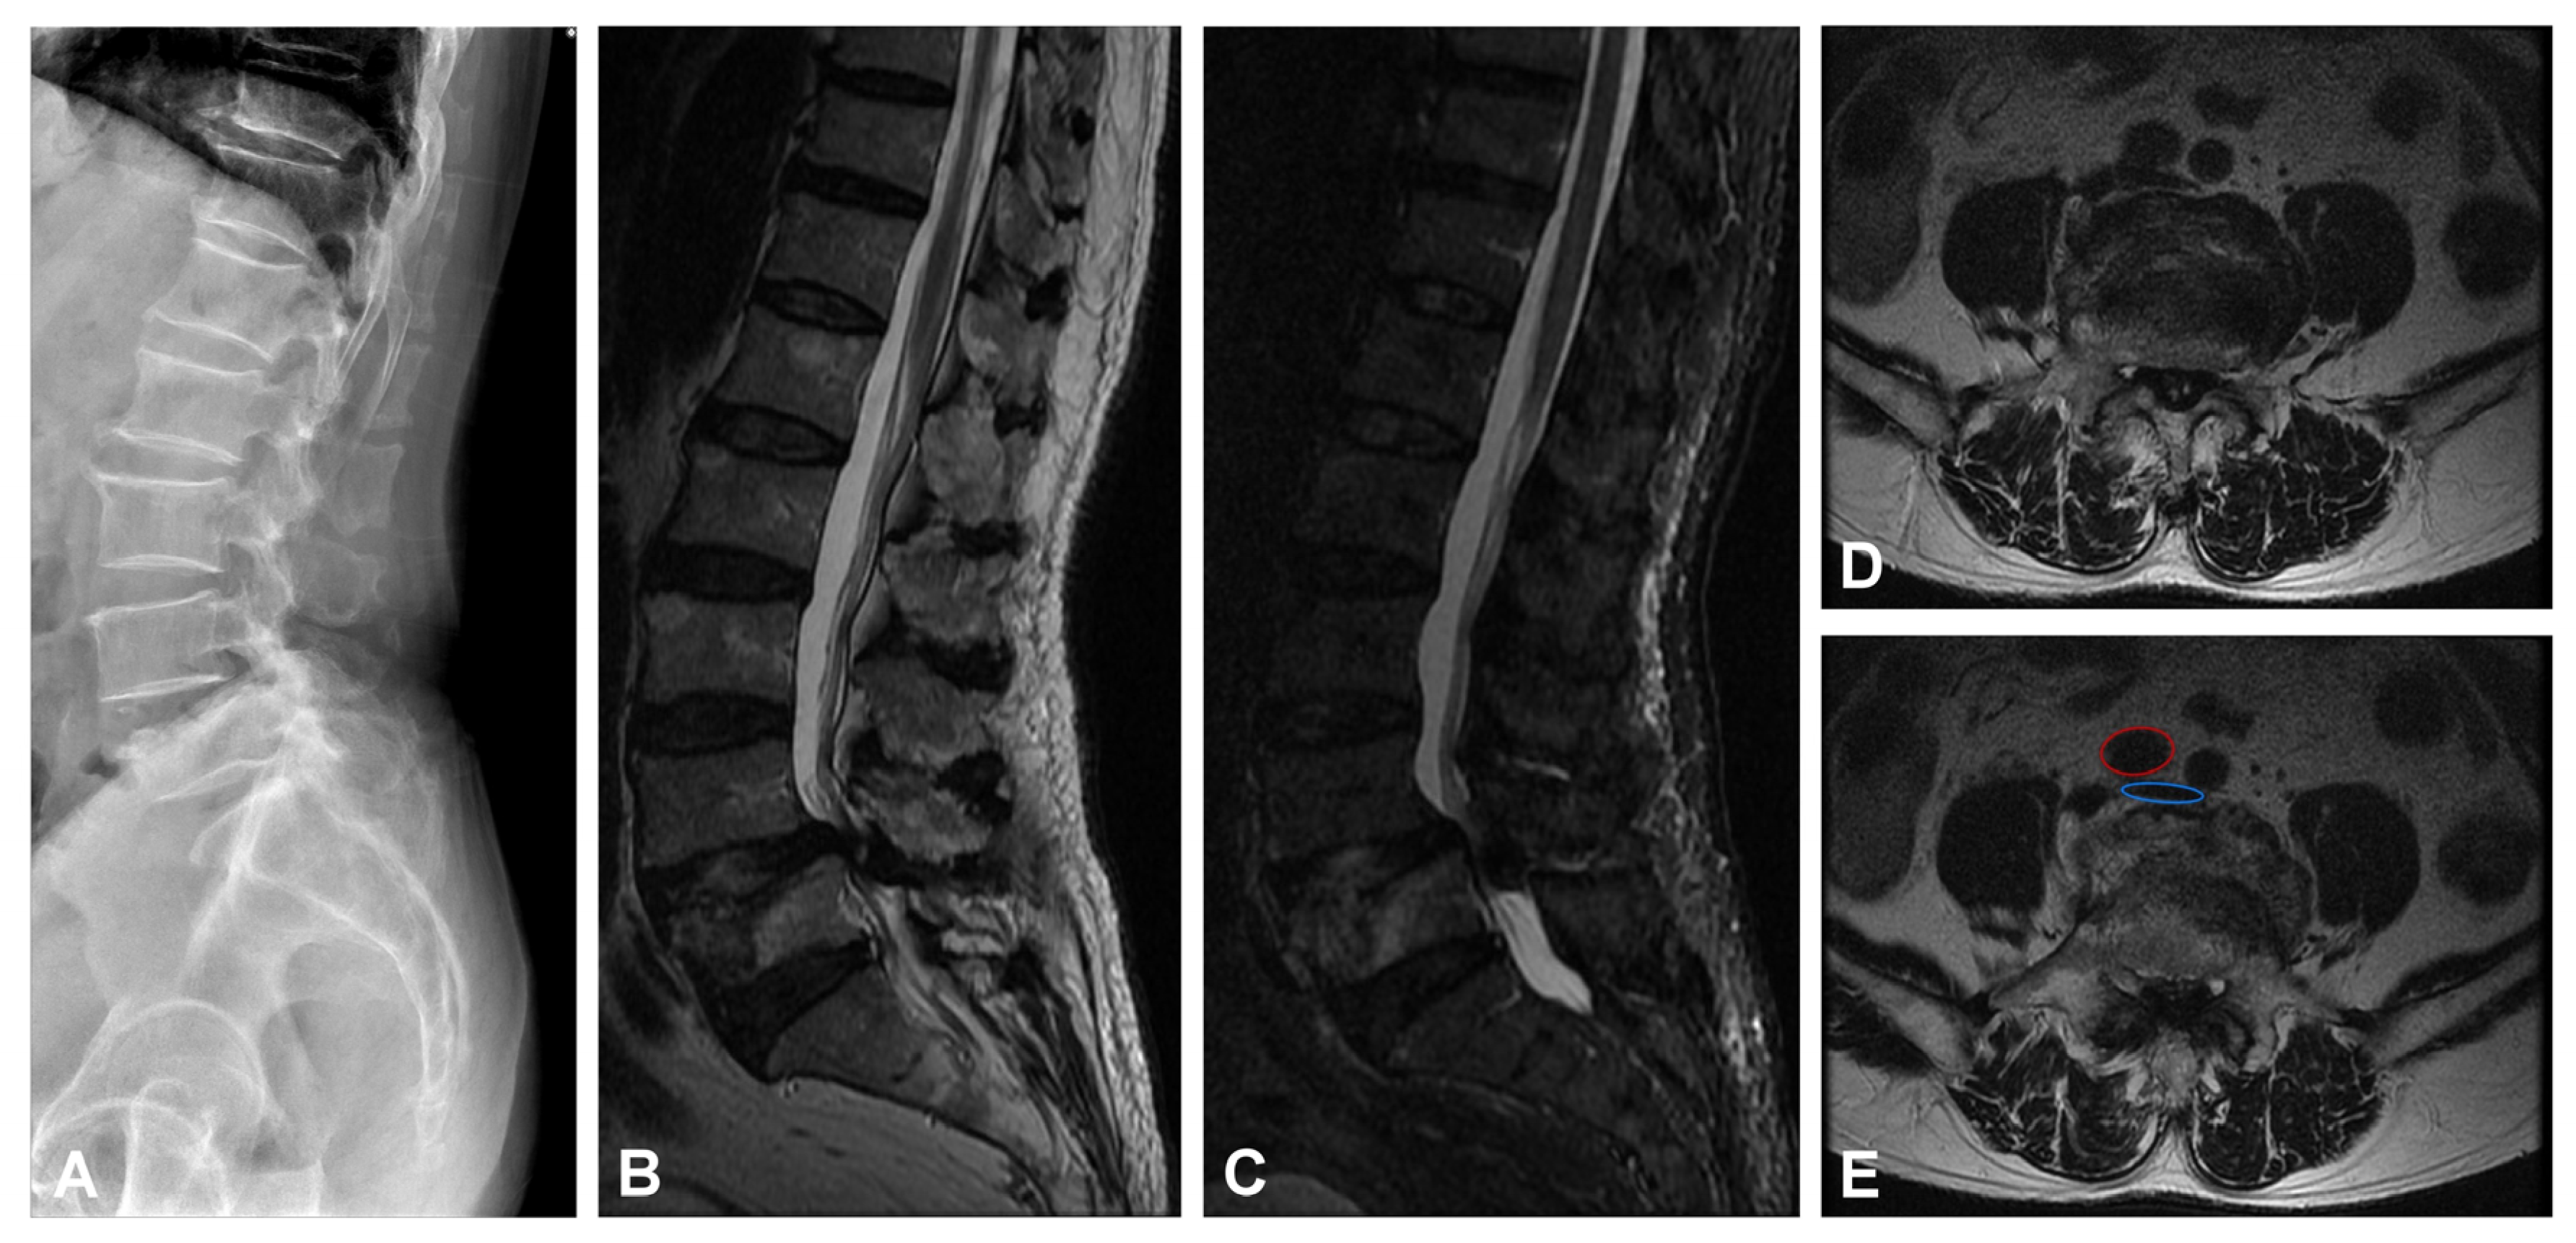

2. Illustrative Case